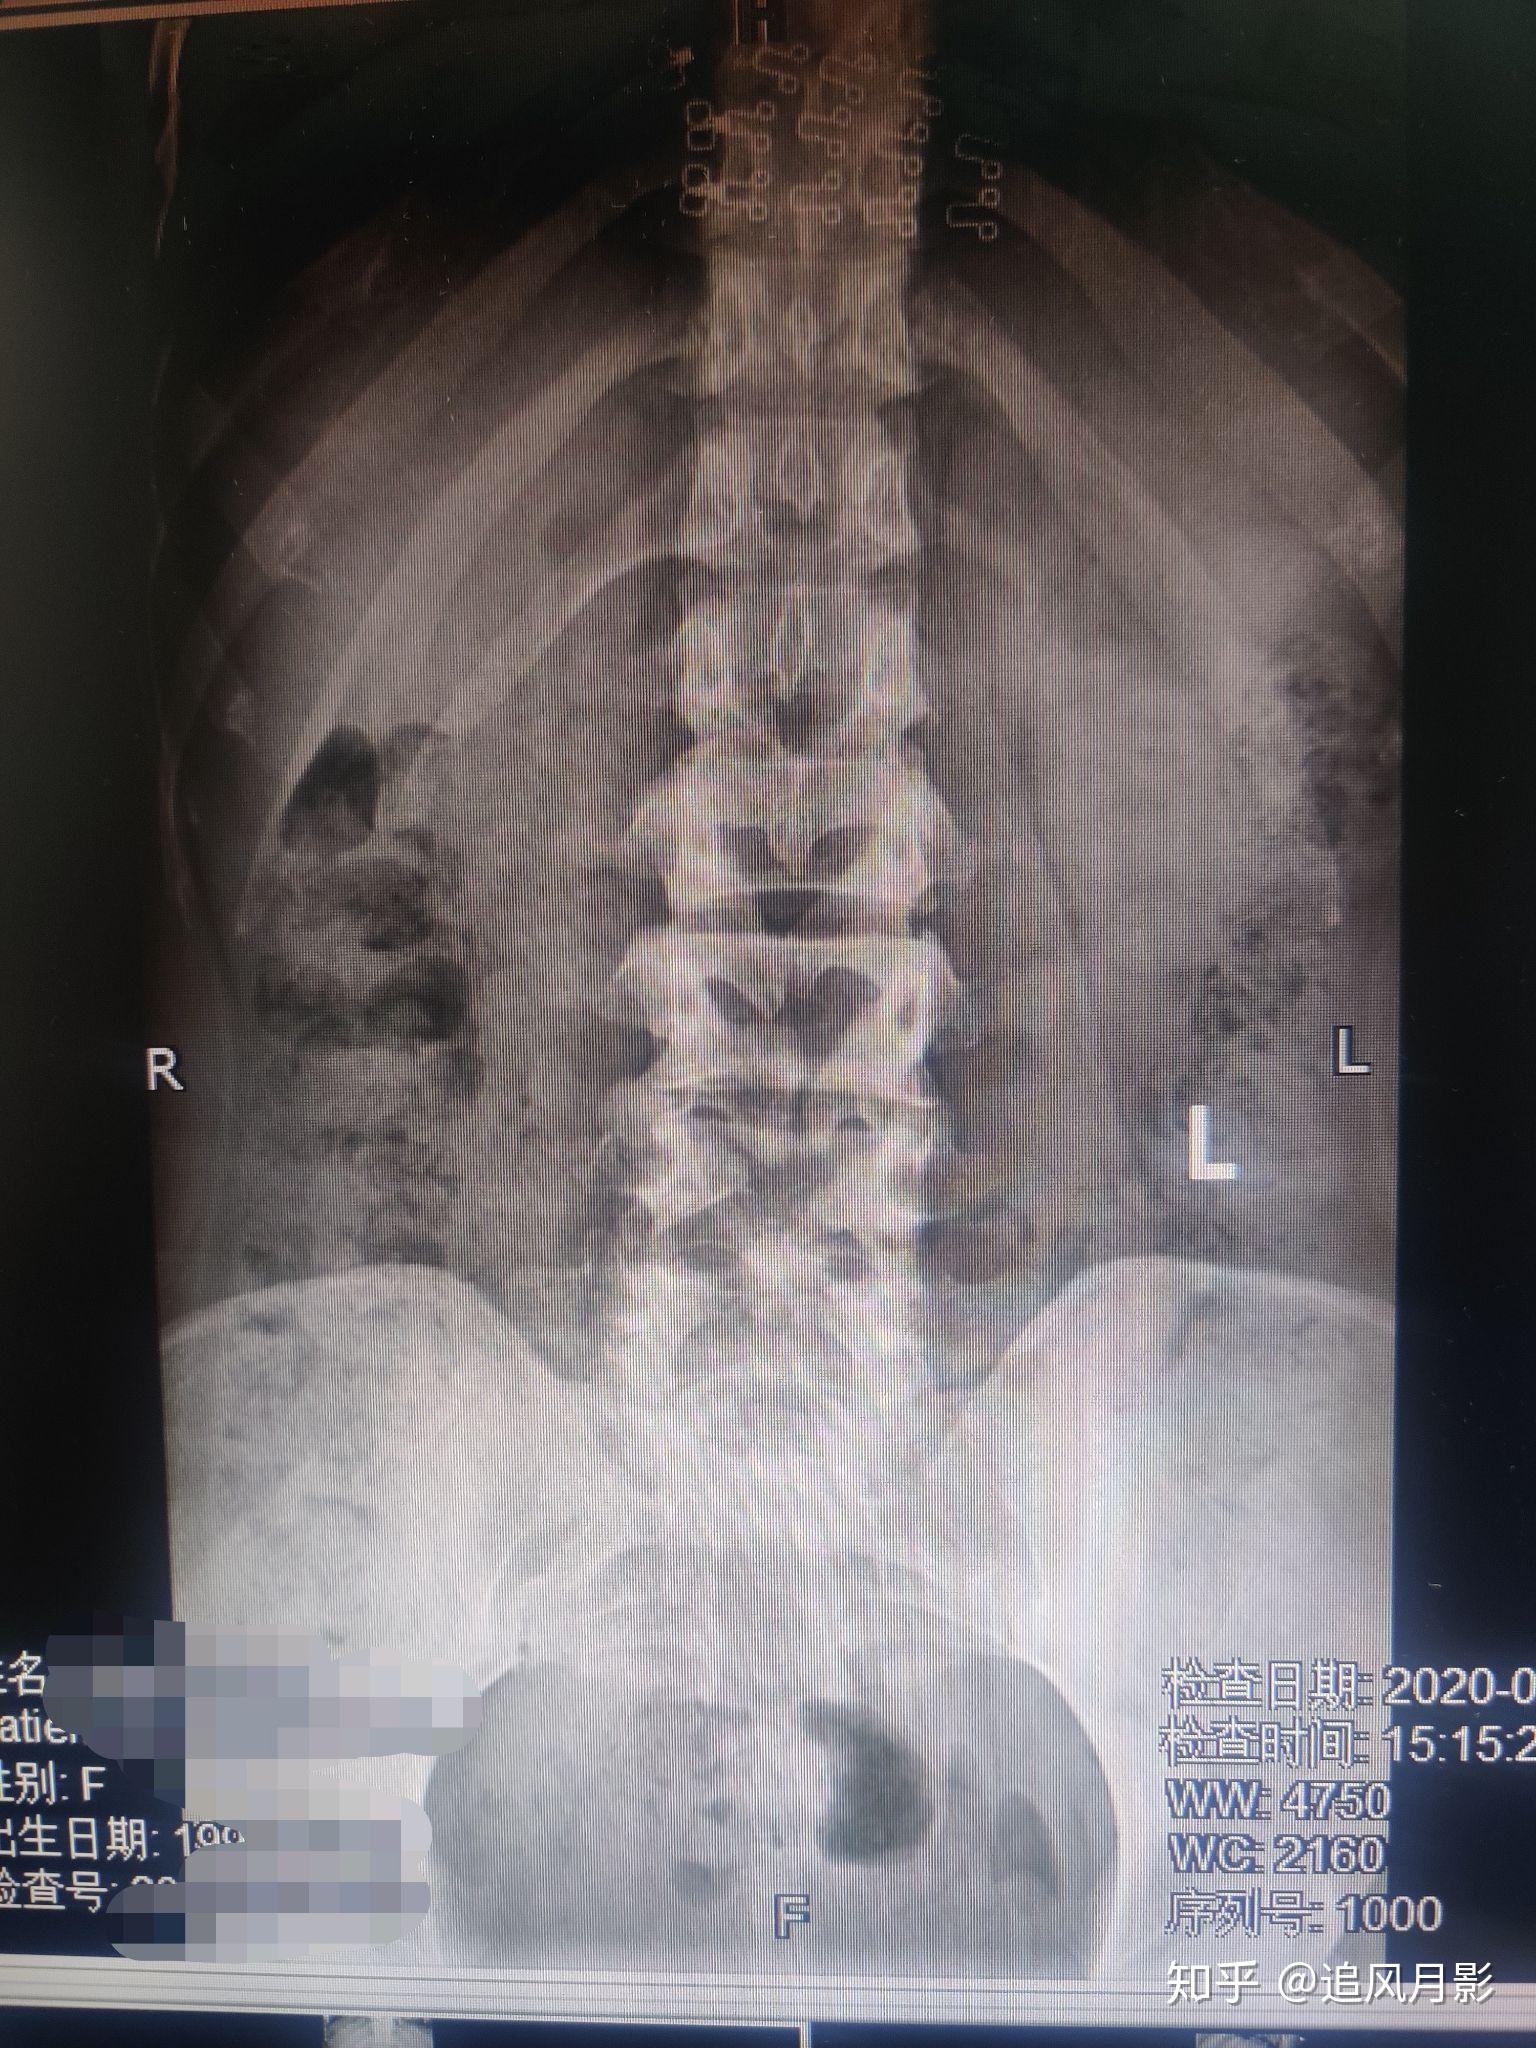

多节段显性脊柱裂,周末门诊坑真多.

图片尺寸1536x2048

多节段显性脊柱裂周末门诊坑真多